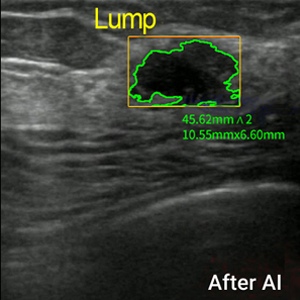

Intelligent Breast Health Screening

Al-Powered Efficiency

Trained on Over 10 Million Images,

Following BI-RADS Standards

Making breast health assessments more accessible and efficient

Dr. J uses advanced deep-learning AI to make ultrasound-based breast health assessments

more accurate and efficient than ever before. It empowers non-experts to perform

standardized, high-quality early screenings, reducing the need for specialized doctors in

initial assessments.